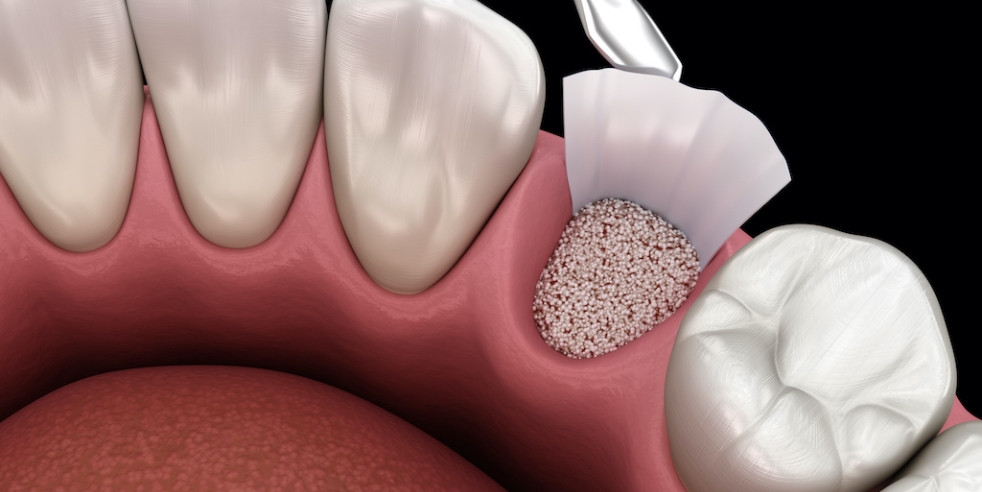

If bone shrinks away from your teeth, it never grows back. In some cases, bone can be encouraged to fill in with grafting materials placed by Dr. Ledesma. Every situation presents a different scenario, but more options than ever exist to promote bone repair in the jaw. For example, when a tooth needs removal, a large hole then exists in the bone. While it will eventually fill in, the site tends to shrink, drawing bone away from the area jeopardizing surrounding teeth. Grafting materials can be placed at the time of tooth removal to help preserve the existing bone level. Bone grafts are especially beneficial if you are considering an implant-supported restoration in the future.

Even areas that have already suffered bone collapse can often benefit from specialized grafting material, bolstering nearly any part of the jaw bone. It’s important to note: bone destroyed by gum disease often leaves significant defects around teeth. While some of these areas are grafting candidates, many of them experience irreversible bone loss. Controlling gum disease with your Aesthetic Smiles Studio team will serve your health much better than corrective surgical grafts.